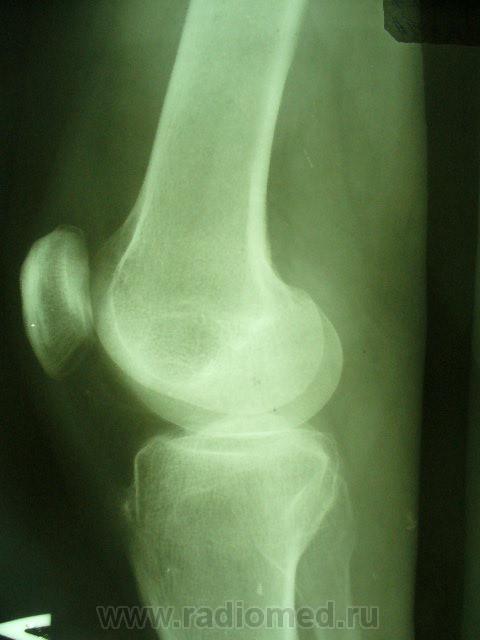

Уважаемые коллеги. Не так давно на странице сайта обсуждалась тема гипердиагностики ДОА. Хотелось бы увидеть ваше мнение по поводу наличия/отсутствия ДОА на представленных снимках. Лет 8 назад попал в автодорожку где-то в другом регионе, там же лечился в НИИТО (со слов, т.к. документов никаких нет) и там же наблюдался с DS: ДОА правого к/с IIст. Переехал в наш регион и решил пройти МСЭК для получения группы инвалидности. Снимки перевернуты, чтобы скрыть маркировку. Так есть ли ДОА?

Едва заметное сужение суставной щели только в левом к/с. На каком основании ДОА?

На мой взгляд - "норма".

Латерализация обоих надколенников, мелкий остеофит по верхнему краю правого надколенника, вытянутость и заострение межмыщелковых отростков левой б/б кости.

Прямая проекция сделана одним лучем на одной пленке, это я их "разделил". Может, из-за этого латерализация? Остеофит левого надколенника есть, никуда не денешься, но ставят артроз (обезображивающий по Рейнбергу) справа.

Вот что хотелось бы уточнить---а что это у нас с межмыщелковыми возвышениями справа???? а что это за окостенение по наружному контуру латерального мыщелка бедра??? ТРАВМА В АНАМНЕЗЕ!!!! Так что - справа - норма? Извините - не уверен. Група не только по снимкам определяется...функция тоже учитывается. А если сделать пару снимков для оценки межмыщелкового углубления и этих самых возвышений.

Выбирай, не выбирай..., а получается только гетерогенное окостенение у внутреннего надмыщелка правой бедренной кости. А с инвалидностью? Косинская как раз и работала в Ленинградском институте экспертизы трудоспособности инвалидов: 2 ст. = 2гр., 3 ст. = 1 гр., в данном случае - никакой группы. Молодцы травматологи, вылечили человека в НИИТОУлыбаюсь!

Нет проблем, пускай обосновывают артроз по своим травматологическим (клиническим) критериям. КТ/МРТ, артроскопия, можно запрос в приснопамятный НИИ сделать. Достоверных, "неубиваемых" рентгенологических признаков артроза нет.

А почему так явно сточены межмыщелковые возвышения справа,  и вопрос: раз рядом с коленом палец - значить его придерживали, или может вообще фиксировали, как палец оказался на снимке? Последнее могло повлиять на рентген картину.

Все правильно замечено. Это, конечно не пальцы, а дополнительные фрагменты костной структуры. Была травма, больной лечился в ИТО. Вероятно, это окостеневшие фрагменты связок, хряща или чего там еще. И межмыщелковое возвышение "изгрызано", м.б. был перелом верхушек. Но ведь это все это не является R- признаками ДОА. Цель демонстрации - выяснить, есть ли рентгеновcкие признаки обезображивающего остеоартроза?